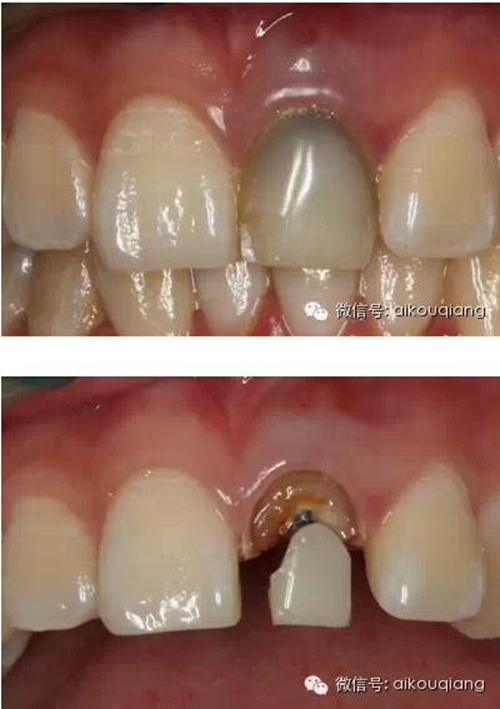

下面是最近處理的一個病例

患者外院螺紋樁核加樹脂冠

唇側(cè)出現(xiàn)瘺管